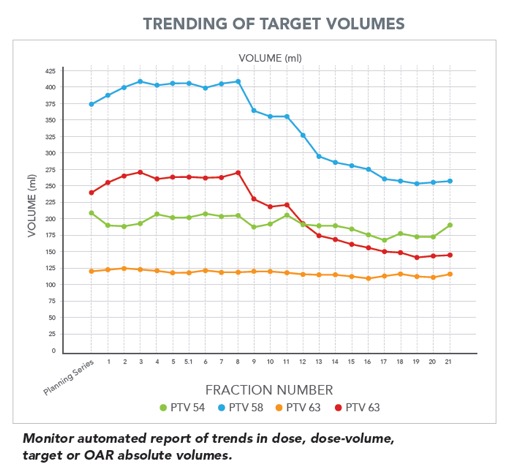

Το σύστημα διαθέτει εργαλεία για την αξιολόγηση των καθημερινά χορηγούμενων κατανομών δόσης επιτρέποντας στους ιατρούς να αναγνωρίσουν πια πλάνα χρειάζονται αναπροσαρμογή.

Το σύστημα διαθέτει εργαλεία για την αξιολόγηση των καθημερινά χορηγούμενων κατανομών δόσης επιτρέποντας στους ιατρούς να αναγνωρίσουν πια πλάνα χρειάζονται αναπροσαρμογή.

- Αξιολόγηση της ευθυγράμμισης του ασθενούς σε θέση θεραπείας.

- Αξιολόγηση των ανατομικών και βιολογικών μεταβολών του ασθενούς κατά τη διάρκεια της ακτινοθεραπευτικής αγωγής

- Αξιολόγηση της καθημερινά χορηγούμενης κατανομής δόσης, της αθροιστικής δόσης μέχρι την συγκεκριμένη συνεδρία καθώς και των δοσιμετρικών διαφορών

- Αξιολόγηση της ανταπόκρισης του ασθενούς στην ακτινοθεραπευτική αγωγή.